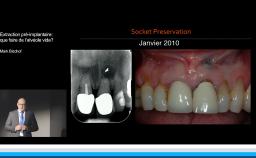

Edentement au secteur anterieur: le défi pour une esthetique optimale

A partir de la description des facteurs de risque esthétique du bloc incisivo-canin maxillaire, de la présence d’os et de gencive autour des implants, le conférencier présente une succession de cas cliniques décrivant ses procédures chirurgicales et prothétiques.

- de déterminer le bon timing de chirurgie implantaire post extractionnelle

- de réfléchir sur la préservation à moyen-long terme de l’os autour des implants